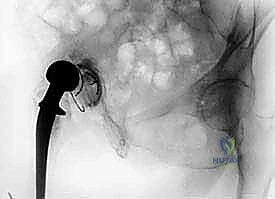

* التصوير الشعاعي: الأشعة السينية (X-rays) لملاحظة أي تخلخل في المفصل أو تآكل في العظام. في حالات معقدة، قد يتم استخدام الأشعة المقطعية (CT scan) أو الرنين المغناطيسي (MRI) المتوافق مع المعادن.

* شفط سائل المفصل (Joint Aspiration): وهو الإجراء الأهم والأكثر حسماً. يتم سحب عينة من السائل المحيط بالمفصل بإبرة دقيقة تحت التخدير الموضعي، وإرسالها للمختبر لزراعتها وتحديد نوع البكتيريا بدقة، لمعرفة المضاد الحيوي المناسب لها.

- الاستخراج المعقد (Implant Removal): يتم فتح المفصل بحذر شديد لحماية الأنسجة المتبقية. يقوم الدكتور هطيف باستخدام أدوات جراحية دقيقة ومتخصصة لإزالة المفصل الصناعي القديم (الساق المعدنية، الكوب الحُقي، والمسامير). التحدي هنا هو إزالة هذه الأجزاء دون التسبب في كسور إضافية للعظم الذي قد يكون هشاً بسبب العدوى.

- التنظيف الجراحي الجذري (Radical Debridement): هذه هي أهم خطوة في العملية بأكملها. يتم استئصال جميع الأنسجة الميتة، المصابة، والملتهبة. يتم كشط العظم حتى الوصول إلى نسيج عظمي حي ونازف. يستخدم الدكتور هطيف تقنيات الجراحة المجهرية الدقيقة للتأكد من عدم ترك أي خلية مريضة، مع الحفاظ على الأنسجة السليمة والأعصاب والأوعية الدموية. يتم غسل التجويف بلترات من المحاليل المعقمة والمطهرات الطبية.

- تشكيل ووضع المباعد الأسمنتي (Antibiotic-Loaded Cement Spacer): بعد التأكد من نظافة الحقل الجراحي، يقوم الجراح بخلط "أسمنت عظمي" طبي مع جرعات عالية جداً من المضادات الحيوية (يتم اختيارها بناءً على المزرعة البكتيرية السابقة).

- يتم تشكيل هذا الأسمنت ليأخذ شكل مفصل الورك المؤقت.

- وظيفة المباعد: يحافظ على طول الساق، يمنع انكماش العضلات المحيطة بالورك، والأهم من ذلك: يقوم بإفراز تركيزات عالية جداً من المضادات الحيوية مباشرة في مكان العدوى على مدار الساعة، وهو ما لا يمكن تحقيقه بالأدوية الفموية.